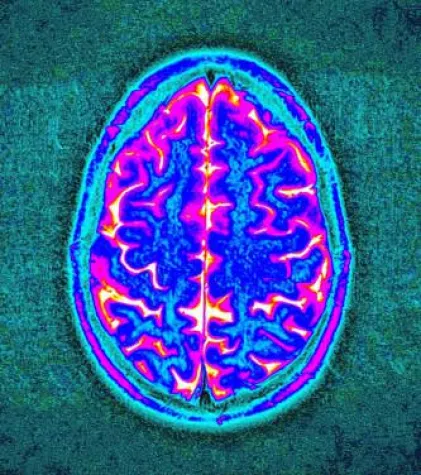

Das internationale Forscherteam identifizierte zwölf Regionen im Erbgut von Migränepatienten, welche für das Risiko, an Migräne zu erkranken, mitverantwortlich sind. Acht dieser Regionen wurden in der Nähe von Genen entdeckt, die eine Rolle in der Kontrolle von Hirnschaltkreisen spielen. Zwei der Genregionen sind für die Aufrechterhaltung der normalen Hirn- und Nervenzellfunktion verantwortlich. Die Steuerung dieser Schaltkreise wird als bedeutsam für das genetische Risiko angesehen, an Migräne zu erkranken.

Das Forscherteam geht davon aus, dass viele der aufgedeckten Risikogene wechselseitig funktionell in Kontakt stehen und das Potenzial haben, die interne Regulation von Nervenzellen im Gehirn stören können. Dies führt zur Entstehung von Migräneattacken.

Migräne wird heute als progressive Erkrankung des zentralen Nervensystems aufgefasst. Durch langanhaltende und hochfrequente Migräneattacken entstehen strukturelle Veränderungen im Nervensystem. Eine Reihe von Begleiterkrankungen wird dadurch begünstigt. Diese schließen im neurologischen Bereich Epilepsie, Medikamentenübergebrauchs-Kopfschmerz und Schlaganfall ein, auf dem Gebiet der Psychiatrie Depressionen, Angst- und Panikerkrankungen, im internistischen Bereich Herzinfarkte, koronare Herzerkrankungen und Bluthochdruck.